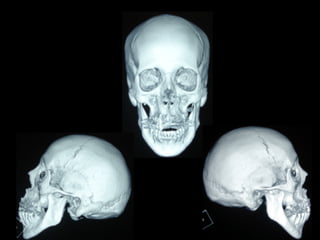

Cefalometría elementalCefalometría elemental

Se observa el número total de órganos dentarios incluyendo

terceros molares.

No hay tratamiento de conductos radiculares

Buen trabeculado óseo de tipo I

Deflección craneal 26º

Longitud craneal anterior 59 mm.

Altura posterior facial 59 mm.

Posición de rama mandibular 78º

Localización de Porión 38 mm.

Arco mandibular 30º

Longitud de cuerpo mandibular 81 mm.